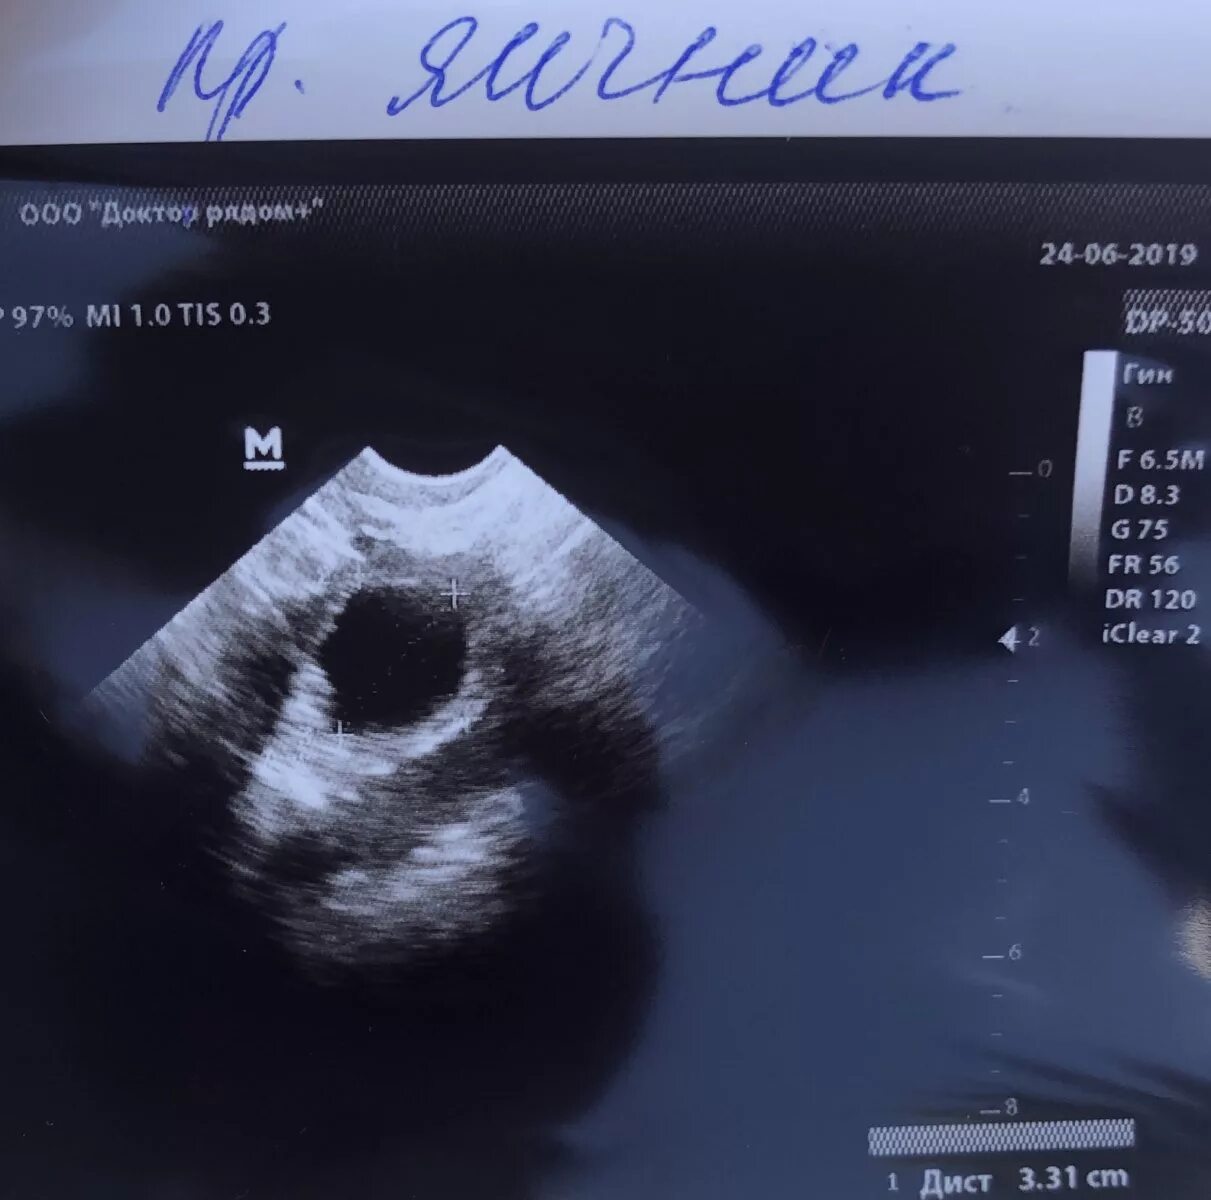

Фолликул 18 мм